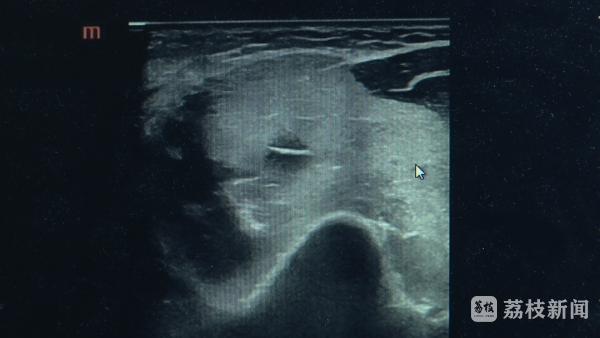

南京市中西医结合医院超声科副主任医师李亚洲介绍广源优配,进行超声检查的时候就发现,肩部上肢的肌肉广泛地肿胀,回声纹理模糊不清,和正常的一看就不一样,因为它的范围比较广,B超看了之后就怀疑这个病横纹肌溶解综合征。